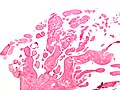

Microscopic

Features:[6]

- Braching papillary fronds which are:

- Composed of collagen, and

- Avascular.

- +/-Elastic tissue.

- Surrounded by:

- Endothelium, and

- Mucopolysaccharide.

Images